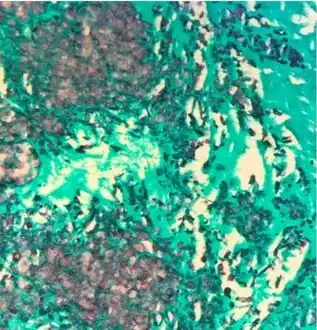

Gomori methenamine silver stain highlights numerous budding yeast and occasional pseudohyphal forms in mitral valve corresponding to C. lusitaniae recovered from culture